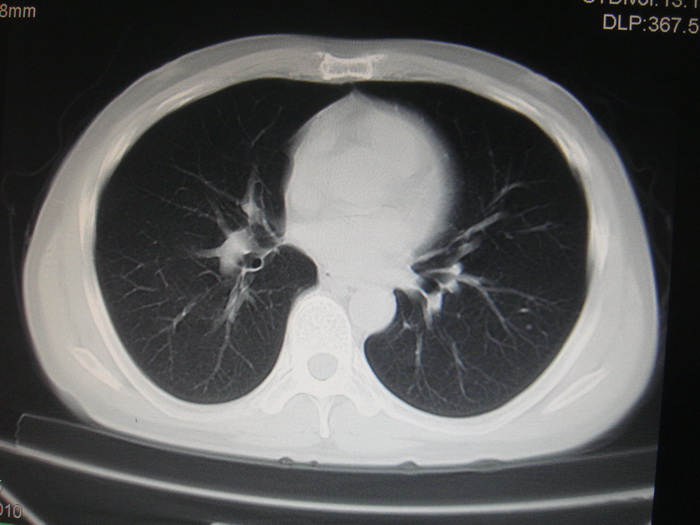

两肺多发结节灶及纵膈淋巴结肿大考虑为转移

两肺多发性转移瘤,纵隔淋巴结转移。

两肺多发性转移瘤,纵隔淋巴结转移瘤。